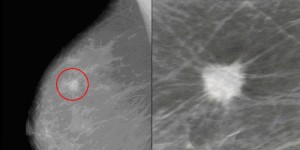

While an ultrasound is very useful for evaluating superficial lumps, a mammogram is better at detecting abnormalities deeper within the breast tissue. Microcalcifications are tiny accumulation of calcium around a tumour and are often picked up on mammograms.

Generally speaking, ultrasound images can't capture microcalcifications. Those tiny calcium deposits can often be some of the earliest signs of breast cancer. However, a mammogram can detect them.

If an abnormality is seen on mammography or felt by physical exam, ultrasound is the best way to find out if the abnormality is solid (such as a benign fibroadenoma or cancer) or fluid-filled (such as a benign cyst). It cannot determine whether a solid lump is cancerous, nor can it detect calcifications.

Why is my breast cancer shadow on ultrasound?

Since cancer tends to be much harder than normal breast tissue, it usually is detectible as a dense shadow on ultrasound. So when it doesn't show up at all, it suggests that whatever is causing the shadow on mammogram is not of different texture than normal, and therefore less likely to be bad.

Since your abnormality did not show on the ultrasound, it may just mean that it is not fluid filled. It does not mean that it is malignant . However, since there is something present on the mammogram, further investigation, such as a biopsy, is needed. actually, not showing on ultrasound can be a good sign.

But since it didn't show on ultrasound, it means the texture of the area is like that of the surrounding tissues. Since cancer tends to be much harder than normal breast ...